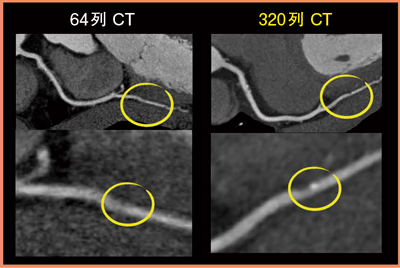

64列CTの画像と320列ADCTの画像を比較してみると,近位部の動きの少ない部分については64列CTでも確認できるが,320列ADCTでは,右冠動脈の遠位側の小さな点状の石灰化や,非石灰化の部分を伴う微細なプラークがきれいに描出されている(図2)。

図2 症例1:64列CTと320列ADCTの比較